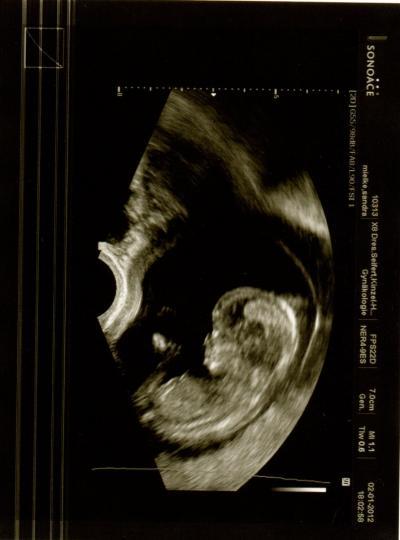

Hallo ihr lieben, war heute beim FA und bin volllll Happy. Unseren Zwerg gehts bestens- ist schon 7 cm groß (ohne Beine)! Es ist alles dran und da wo es hingehört. Herzchen haben wir auch schlagen hören :o) Laut Entwicklung ist der Krümel knapp eine Woche weiter als von der "normalen rechnung"... Die FA meinte, nächstes mal kann man eventuell schon das Geschlecht bestimmen :o) Unser Krümel war fleißig am Bewegen- voll süß Besser hätte das Jahr nicht anfangen können GLG Sandra

Bild zu FA Bericht - Forum für Juli - Mamis

noch mal ein 2tes Bild :o)

Oh super das Gesicht ist ja schon voll zu erkennen die Lippen und die Nase Wahnsinn...als ob es gerade die Nase rümpft und schmollt.... Oh Mann ich bin morgen dran hoffentlich bekomme ich auch so´n tolles Bild wie Du....na da kommt doch Vorfreude auf oder???? Alle Gute für Euch.... LG Steffie